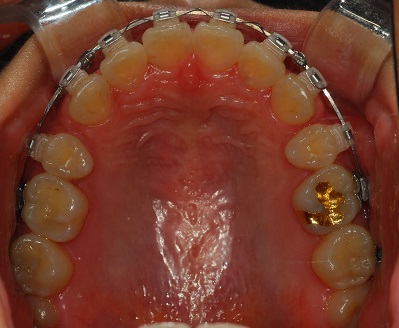

상악 사진

상악과 하악의 발치 공간의 차이가 좀 보이네요